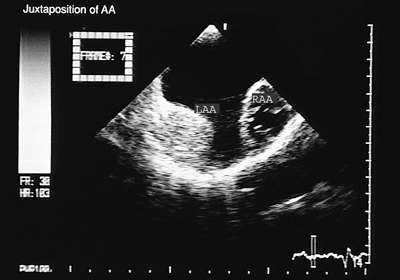

Juxtaposed Atrial Appendages

Juxtaposition is an uncommon malformation in which the two atrial appendages are located on the same side of the great vessels. Left juxtaposition is six times more frequent than the right-sided one and is usually associated with discordant V–A connection, which may be isolated or may be combined with the absence of right A–V connection. The identification of this malformation is important, particularly when a procedure such as a Rashkind septostomy or a Mustard, Senning, or Fontan-type surgery is planned.

FIGURE 8.2.16. Juxtaposition of atrial appendages. Transverse plane imaging shows both atrial appendages (LAA, RAA) located on the left side. LA, left atrium; LV, left ventricle; RA, right atrium; RV, right ventricle.

FIGURE 8.2.17. Juxtaposition of atrial appendages. The right atrial appendage (RAA) is imaged more anteriorly as compared to the left atrial appendage (LAA)

Recognition of juxtaposition with transthoracic echocardiography can be difficult in older children or patients with poor acoustic windows. Its angiographic identification requires an intense contrast in both atria and the juxtaposed atrial appendages. Transesophageal echocardiography is considered the technique of choice for identifying this anomaly. The transesophageal features of left juxtaposition of the atrial appendage include (a) right lateral deviation of the inferior and posterior portion of the atrial septum; (b) a more frontal orientation of the anterosuperior part of the atrial septum, forming the floor and the posterior wall of the junction of the right-sided atrial appendage with the venous component of the atrial cavity (Fig. 8.2.16); (c) the two atrial appendages, each with its own morphology, visualized on the same side, either in superior–inferior positions or side-to-side (Figs. 8.2.16 and 8.2.17); and (d) the association of one or various septal defects of the ostium secundum type, which may be difficult to recognize. The abnormal orientation of the atrial septum may give the false impression of an atrial septal defect located at the site of the junction of the atrial appendage with the venous cavity (3).